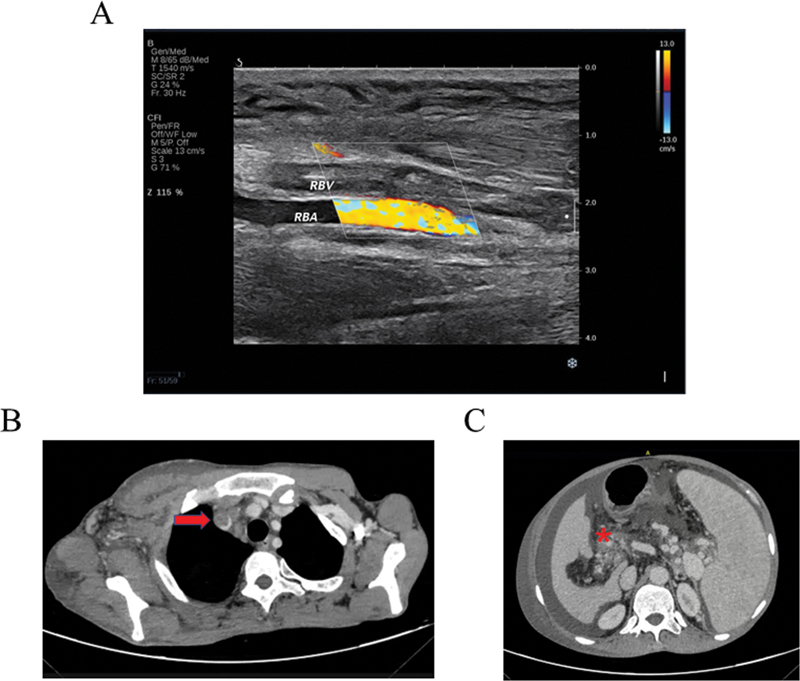

静脉血栓栓塞症(VTE)是一项世界性的健康挑战,每年影响数百万人。静脉血栓的形成部分受到遗传因素的影响。遗传性血栓形成被描述为由基因决定的 VTE 易感性。在本研究中,一名男性患者因在不同部位多次发生静脉血栓而被转诊至我科。鉴于缺乏可识别的风险因素,我们旨在研究静脉血栓形成的可能遗传因素。我们采用了全外显子组测序技术来检测与该患者遗传性血栓性疾病相关的基因。推测的变体随后通过家族内的桑格测序得到确认。经鉴定,该患者携带两种基因突变。一个是新型 c.400G > C (p.E134Q) 突变,影响 PROC 基因第 5 号外显子的最后一个核苷酸,可能会影响剪接。另一个是之前报道过的 SERPINC1 基因中的杂合无义变异 c.1016G > A (p.W339X)。前者由母亲遗传,后者由父亲遗传。该患者出现的双基因遗传反映了静脉血栓形成的复杂表型,并证明了采用无偏见方法检测致病变异的重要性,尤其是在遗传性血栓形成高风险患者中。

Venous thromboembolism (VTE) represents a worldwide health challenge, impacting millions of people each year. The genesis of venous thrombosis is influenced in part by genetic components. Hereditary thrombosis is described as a genetically determined susceptibility to VTE. In the present study, a male patient was referred to our department presenting with multiple venous thrombosis events in different locations. Given a lack of identifiable risk factors, we aimed to investigate the possible genetic factor underlying venous thrombosis. Whole-exome sequencing was employed to examine genes linked to inherited thrombophilia in the proband. Putative variants were subsequently confirmed through Sanger sequencing within the family. The proband was identified as carrying two genetic mutations. One is the novel c.400G > C (p.E134Q) mutation affecting the final nucleotide of exon 5 in the PROC gene, potentially impacting splicing. The other is a previously reported heterozygous nonsense variant c.1016G > A (p.W339X) in the SERPINC1 gene. The proband inherited the former from her mother and the latter from her father. The presence of digenic inheritance in the patient reflects the complex phenotype of venous thrombosis and demonstrates the significance of an unbiased approach to detect pathogenic variants, especially in patients with a high risk of hereditary thrombosis.